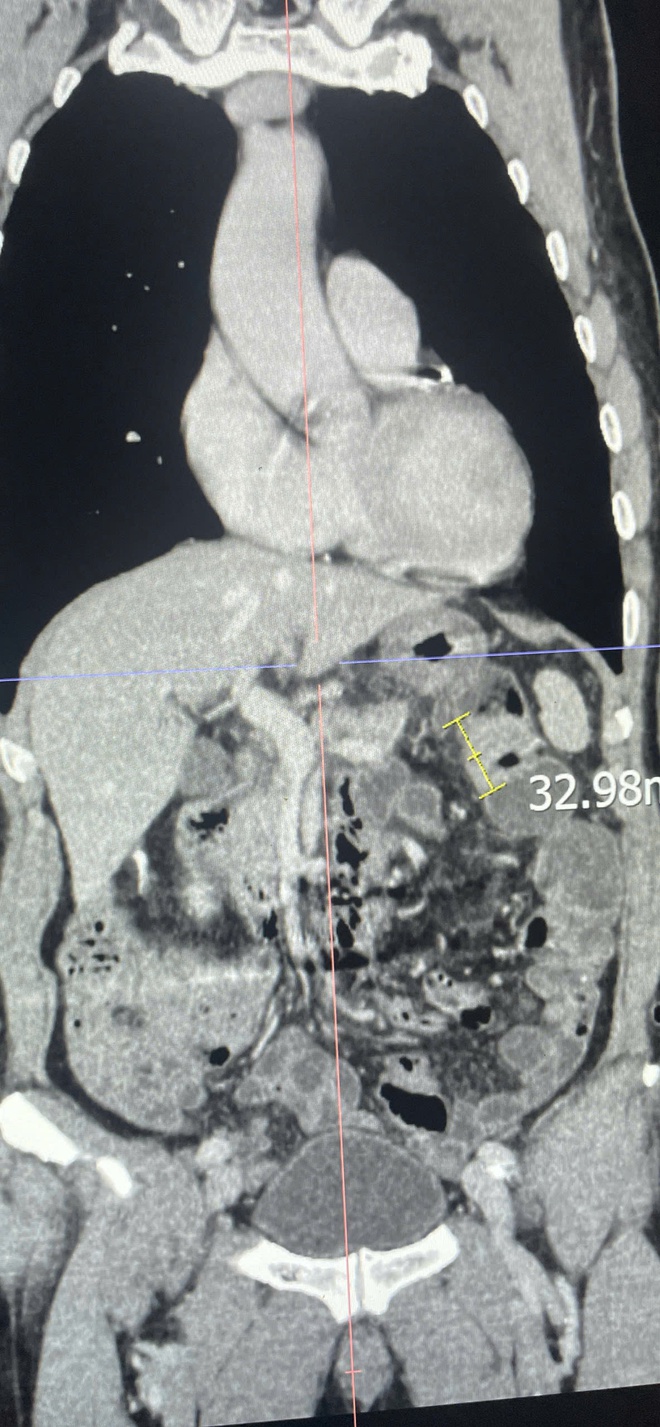

Kết quả xét nghiệm cho thấy bệnh nhân bị thiếu máu nặng, biểu hiện của tình trạng mất máu mạn tính. Trước dấu hiệu bất thường này, các bác sĩ đã chỉ định đánh giá lại toàn diện bằng nội soi dạ dày, nội soi đại tràng, làm các xét nghiệm tổng thể đánh giá nguyên nhân thiếu máu và chụp cắt lớp vi tính (Cắt lớp vi tính 256 dãy) toàn thân. Kết quả phát hiện một khối u sùi mới tại đại tràng, nhiều khả năng là ung thư tái phát (cần kết quả giải phẫu bệnh để chẩn đoán xác định) và rất nhiều polyp đại tràng.

Hình ảnh dày thành đại tràng góc lách nghi u đại tràng trên phim chụp cắt lớp vi tính 256 dãy toàn thân.